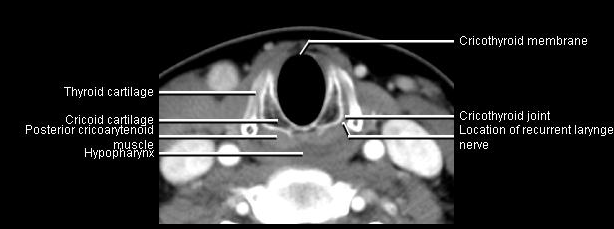

Phonation and dysphagia involve multiple coordinated structures in the larynx and pharynx. Radiation induced dysphagis appears to be related to dose to the phyaryngeal constrictor muscles and specific regions of the supraglottic and glottin larynyx.

Speech is impacted by doses to the epiglottis, base of tongue, aryepiglottic folds, false vocal cords upper esophageal sphincter and cricoid cartilage.

AnatomyCTMR